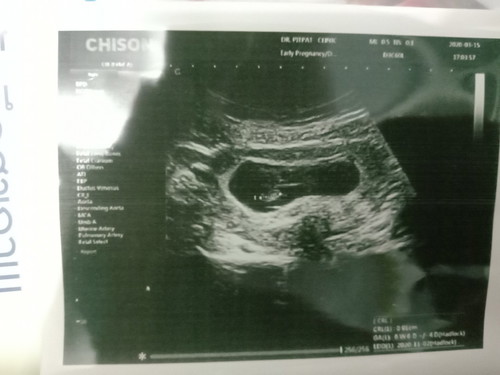

ท้อง5ครั้งพึ่งเจอหัวใจเต้นครั้งแรก ตื่นเต้นสุดๆ

นับจากรอบเดือน 8 w แต่จากผล u/s นับได้ 6 w 6 d แค่นี้ก็ดีใจมากแล้ว